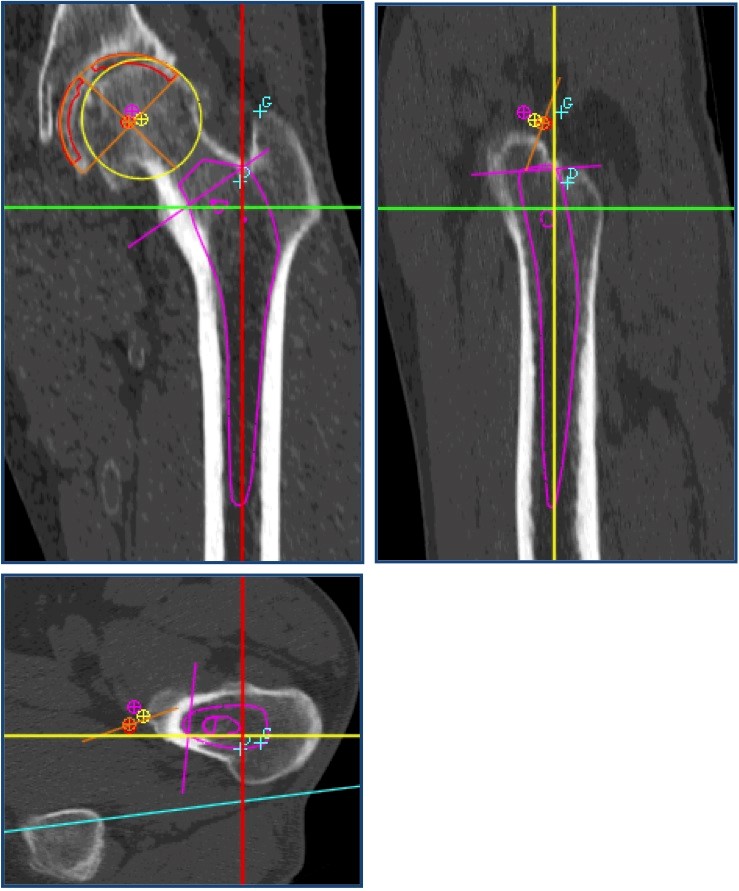

PLANIFICATION PRÉOPÉRATOIRE 3D informatisée sur SCANNER

La planification informatisée sur scanner est couramment pratiquée par un petit nombre de chirurgiens, depuis 2005.

– utilisation d’un logiciel SPÉCIFIQUE de planification en 3 Dimensions

La planification 3D sur scanner apporte une réponse à ces deux problèmes, ce qui offre plusieurs avantages directs :

• Une visualisation de l’articulation et des pièces osseuses dans TOUS les plans

Ces données, stockées sur CD, peuvent être chargées sur un ordinateur personnel et exploitées à l’aide d’un logiciel spécifique « 3D Hip plan »  développé par la société Symbios.

POSITIONNEMENT 3D DES PROTHÈSES « VIRTUELLES »

Le positionnement des prothèses « virtuelles » est alors possible.

L’implant fémoral intraosseux « virtuel » (tige) peut être positionné finement par translations et rotations dans tous les axes de l’espace selon:

• La nécessité d’un centrage 3D « automatique ».

RAPPORT DE PLANIFICATION

Une synthèse en plusieurs pages, incluant les vues tomodensitométriques, les valeurs millimétriques et angulaires de restauration anatomique, peut être éditée sur papier et ainsi être disponible au bloc, consultable avant et pendant l’intervention.